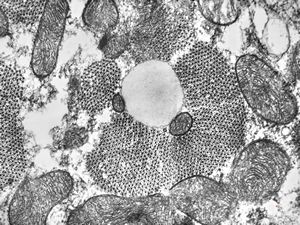

M,21y. | annulate lamellae - intracranial germinoma